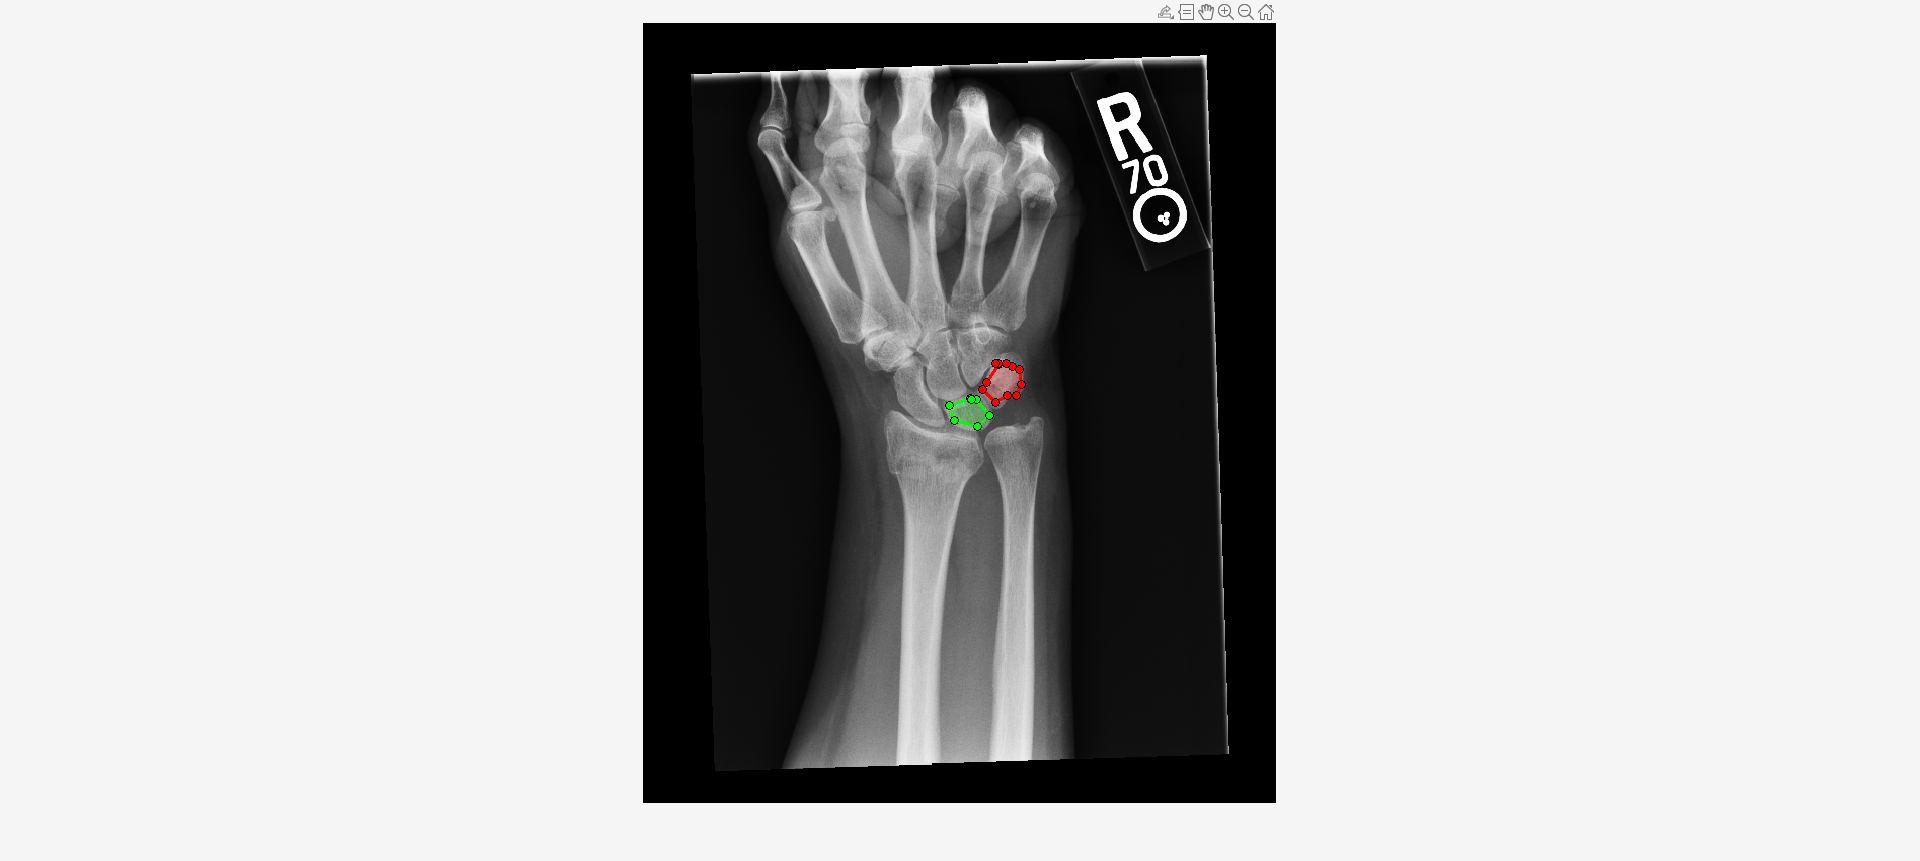

Load an X-ray image into the workspace as a medicalImage object. Visualize the image.

imshow(I,[])Draw two regions of interest (ROI) in the X-ray image. Create masks from the ROIs.

roi1 = drawassisted(Color="g"); roi2 = drawassisted(Color="r");

mask1 = createMask(roi1,I); mask2 = createMask(roi2,I);